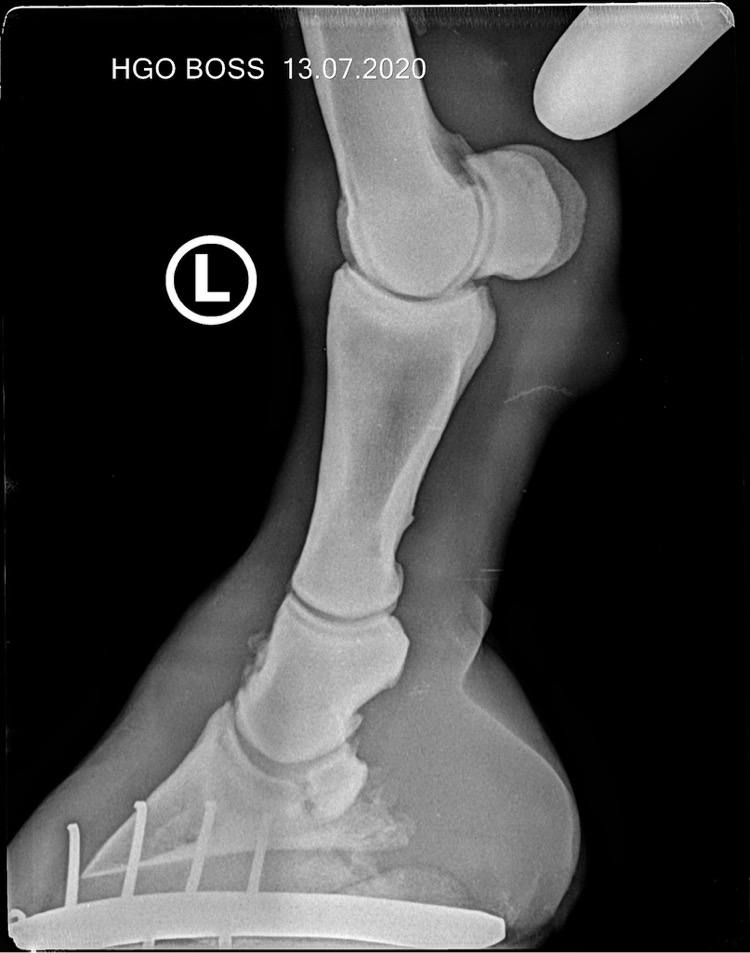

denis23 Опытный 13 Июль 2020 #2 вот рентгены. Вложения 85DB6103-3262-457A-9EC6-C11434451E2D.jpeg 108.6 KB · Просмотры: 196 14D59F73-6819-498E-83C4-FD2539AA5479.jpeg 109 KB · Просмотры: 189